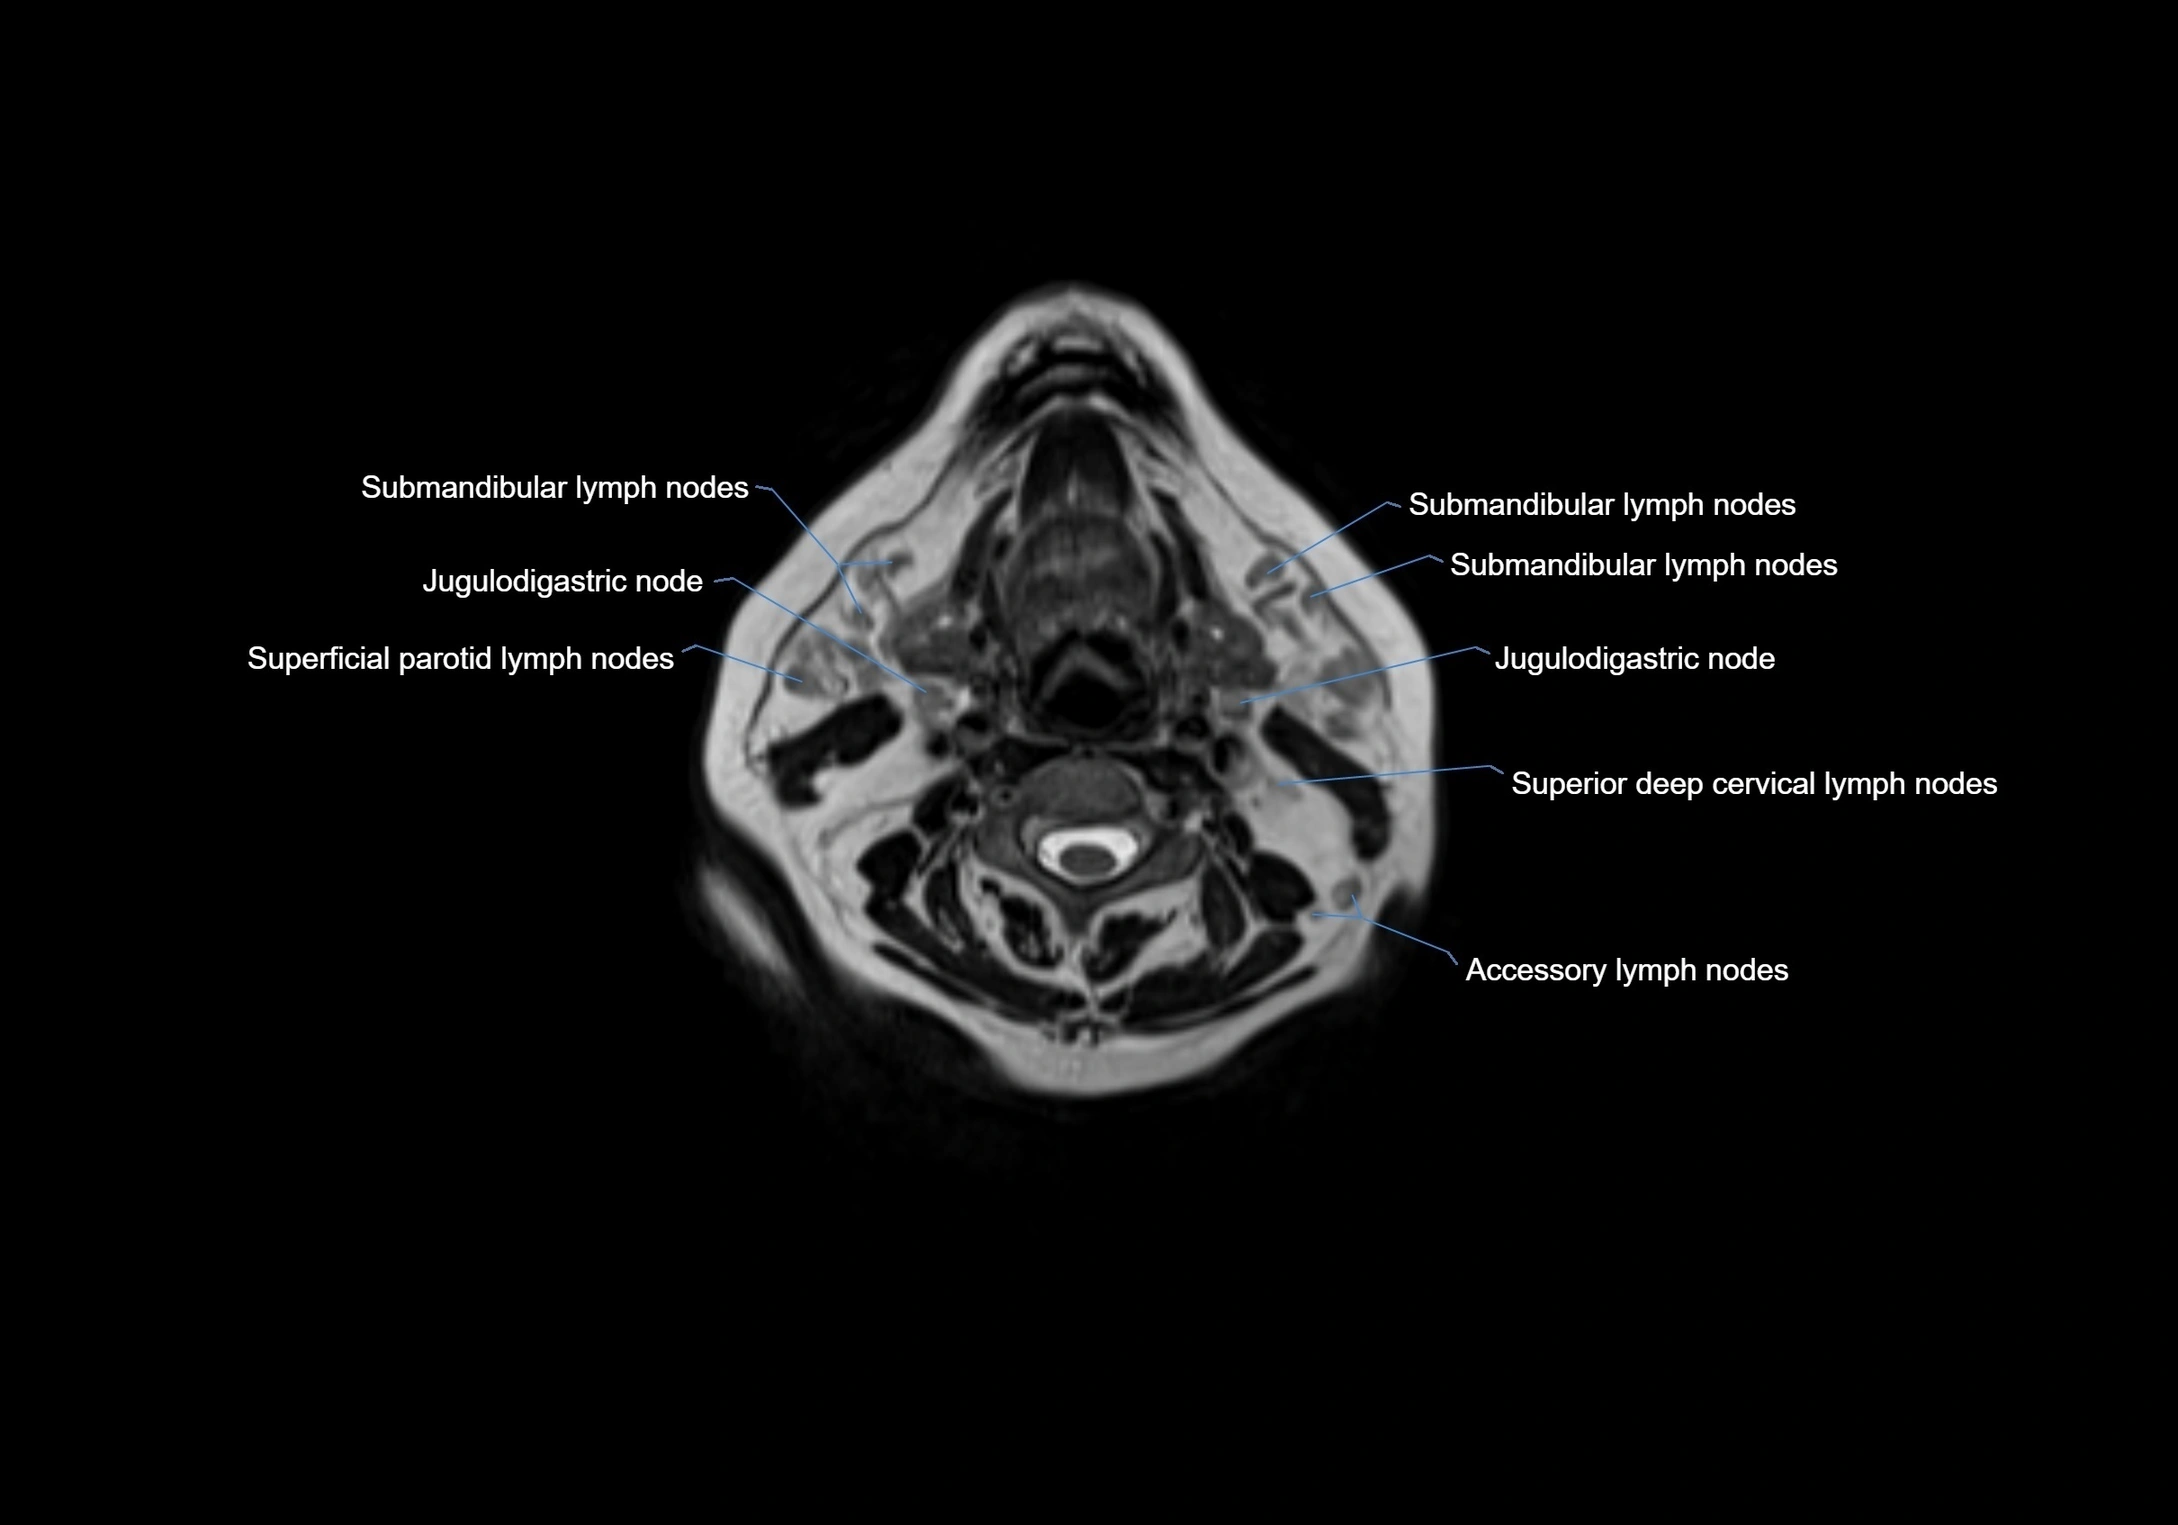

Accessory lymph nodes

Accessory lymph nodes are small, secondary lymph nodes located along the main facial and cervical lymphatic chains, often adjacent to primary lymph nodes, such as preauricular, submandibular, or occipital nodes. They are typically less than 5 mm in diameter, embedded within subcutaneous fat or connective tissue, and may be variable in number and location. These nodes provide additional filtration and immune surveillance for lymph collected from the face, scalp, and neck regions. Accessory lymph nodes are usually non-palpable in healthy individuals but may enlarge in response to infection, inflammation, or metastasis, making them clinically significant.

Location

• Found along primary lymph node chains, including preauricular, submandibular, parotid, and occipital regions

• Embedded in subcutaneous fat or superficial fascia, often lateral or posterior to primary nodes

• Variable in number; may occur unilaterally or bilaterally, depending on individual anatomy

MRI images

image